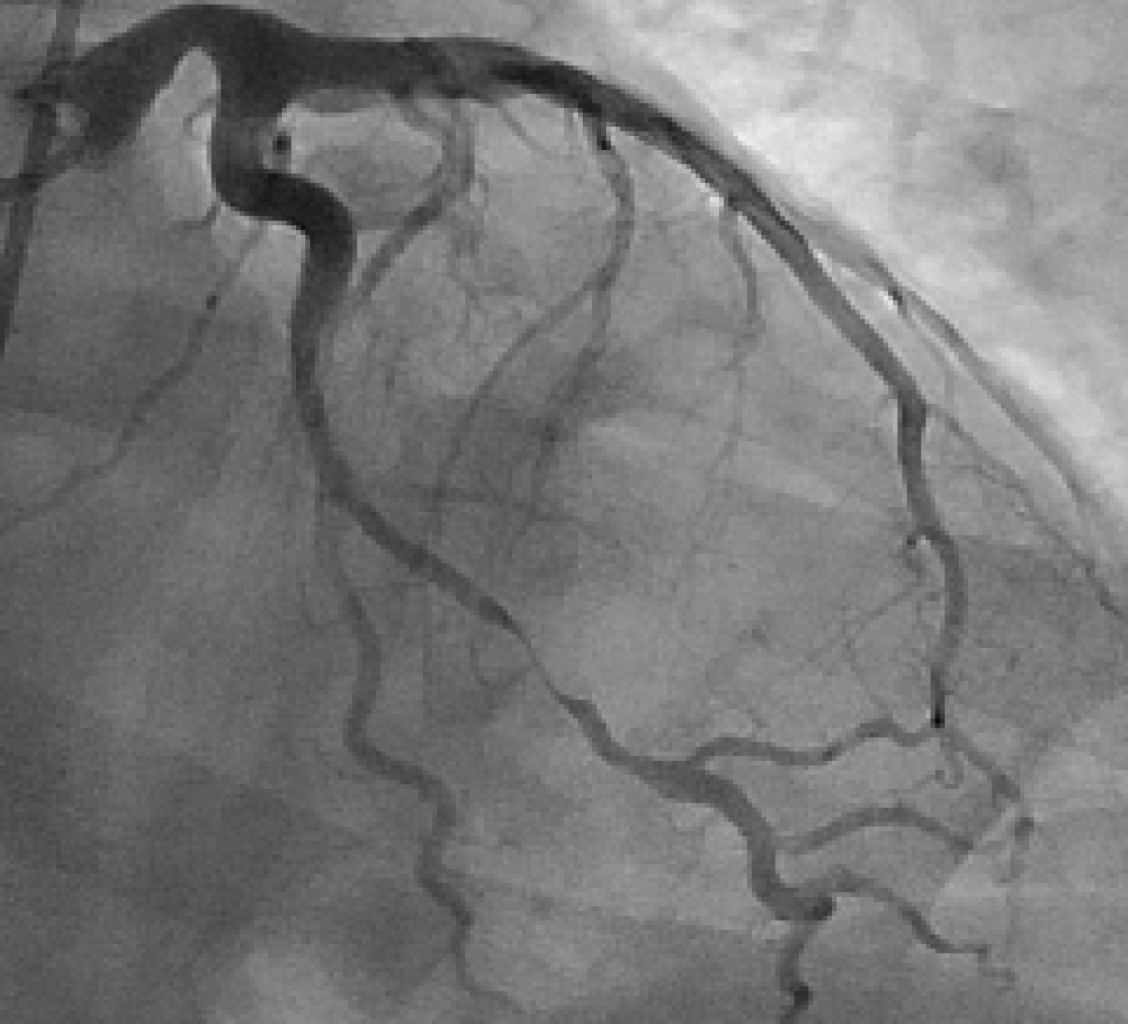

Disección coronaria espontánea asociada a ejercicio como causa de parada cardíaca

Figura 1

Figura 2

Figura 3